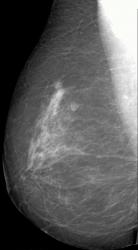

СЛУЧАЙ РЫБАКОВОЙ Л. А. "Инфильтрирующий рак правой молочной железы".

"Инфильтрирующий рак правой молочной железы".